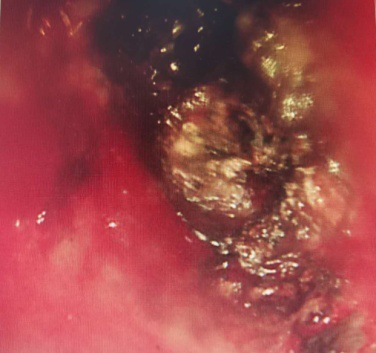

為進一步明確診斷,緩解患者氣短癥狀,入院后積極完善相關(guān)檢查,經(jīng)過全科討論后并制定針對突發(fā)情況的預(yù)案,在全身麻醉下經(jīng)喉罩插入電子支氣管鏡檢查,于左上葉支氣管開口可見新生物完全堵塞管口,病變表面有壞死,在病變處給予活檢,鏡下初步診斷肺癌,遂立即給予氬氣刀消融治療,過程順利,治療后可見左側(cè)固有段和舌段分支開口。術(shù)后氣短癥狀明顯減輕。患者和家屬非常滿意 。

術(shù)中